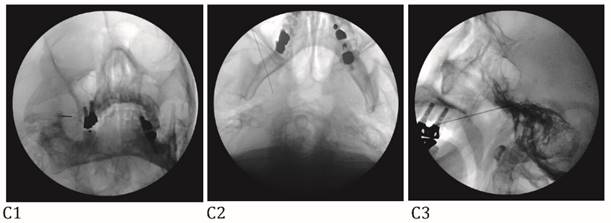

The Tnbs were performed with fluoroscopic guidance. Peripheral branch blocks including infraorbital nb (IONB) and supraorbital nb (SONB) and major branch blocks including maxillary nb (V2), mandibular nb (V3), and combined maxillary and mandibular nb (V2+3) were performed according to pain site of an individual patient. All study Tnbs were used pure alcohol (Dehydrated Alcohol Injection, USP, Tera Pharmaceuticals, Buena Park, CA, USA) after the confirming accurate needle position on the fluoroscopic view (Fig. 1) and diagnostic hypesthesia on the pain site using injection of 1% lidocaine with same doses of alcohol for neurolytic block. Total volume of alcohol for the Tnbs were; 0.3~0.5 ml for SONB, 0.5 ml for IONB, 0.5~1 ml for V2, 0.3~0.7 ml for V3, and 0.15~0.2 ml for V2+3.

Figure 1

A: Maxillary nerve block. A needle tip is located right lateral to foramen rotundum on the anteroposterior view (A1) and pterygopalatine fossa on the lateral view (A2). B: Mandibular nerve block. A needle tip is placed at the midportion of the foramen ovale on the anteroposterior oblique view (B1). At this point, a needle is advanced a few millimeters medially to elicit paresthesia in the V3 innervated area. When the proper paresthesia is achieved, a needle tip should be in a cross point of the lateral one-third of the perpendicular line and the midhorizontal line of the foramen ovale on the submentomandibular view (B2). On the lateral view, a needle is placed in the entrance of foramen ovale at the margin of petrous bone (B3). C: Combined maxillary and mandibular nerve block. A needle tip is placed at the midportion of the foramen ovale on the anteroposterior oblique view (C1). At this point, a needle is advanced a few millimeters cephalad passing foramen ovale on the submentomandibular view (C2). On the lateral view, a needle is placed passing foramen ovale a few millimeters under the clival line (C3).